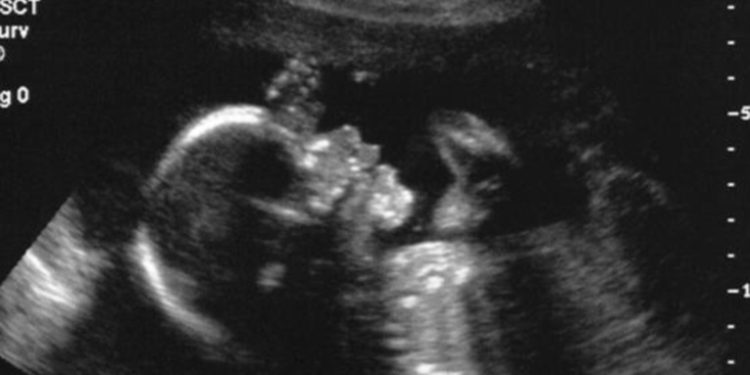

En una primicia mundial, unos médicos cirujanos han logrado operar exitosamente una malformación del cerebro de un feto de 34 semanas y 2 días de gestación, mientras este todavía se encontraba en el útero, según se describe en un estudio publicado este jueves (04.05.2023) por la revista Stroke.

Con la ayuda de una ecografía, los doctores utilizaron una técnica quirúrgica llamada embolización para tratar una malformación de la vena de Galeno, una rara afección prenatal que afecta al cerebro y que suele tratarse después del nacimiento.